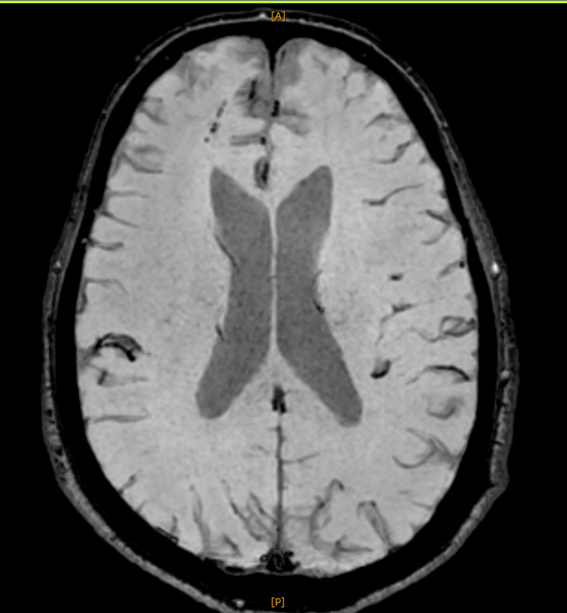

以下、今回撮られたMRI画像です。いずれも 右前頭葉に脳挫傷性の変化 が認められます。

これらは びまん性軸索損傷 の所見です。

脳挫傷やびまん性軸索損傷を示す画像所見が認められることが必要になります。

本件では、上記のとおり、はっきりとした画像上の異常所見があり、これにより脳挫傷、びまん性軸索損傷と診断されました。